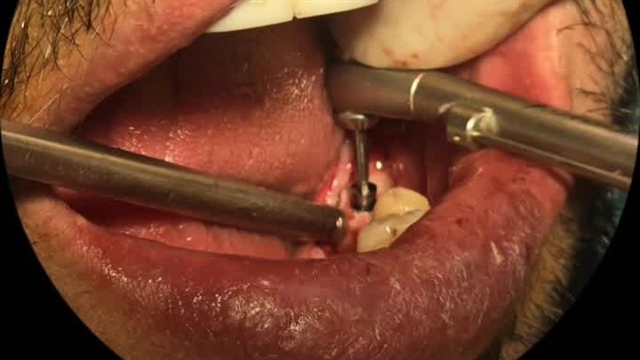

ایمپلنت دندان آقای ملک زاده در کلینیک دکتر حمید پورصادقی